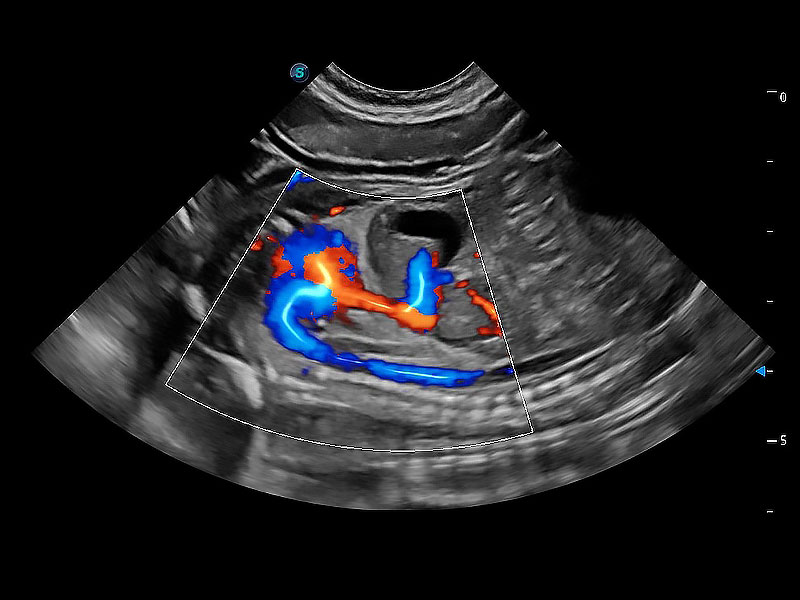

• Bright Flow 立体血流成像

在传统二维血流成像的基础上,呈现血流的立体感,具有动感的生命力之美。即便是微小的血管也能轻松应对,提高了血流的视觉敏感性。